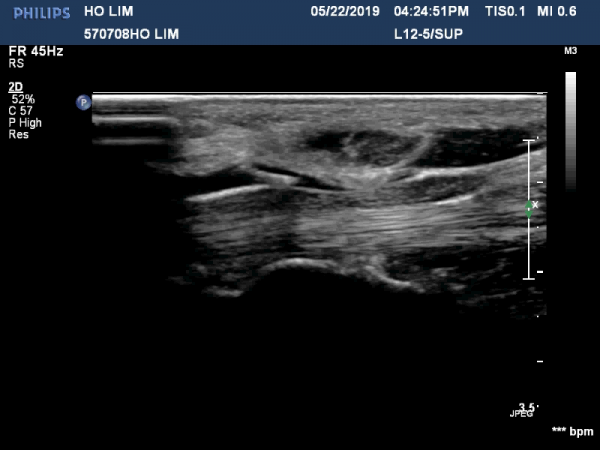

¼ö±Ù°ü ¸»´ÜºÎÀ§(trapezium, capitate level)¿¡¼ Á¤Á߽Űæ Ⱦ´Ü¸é°Ë»ç»ó Á¤Á߽ŰßÀÇ ÆíÆòȰ¡ °üÂûµÊ(»çÁø 3).

Á¤Á߽Űæ Á¾´Ü¸é°Ë»ç»ó ¼ö±Ù°ü ¸»´Ü(trapezium, capitate level) µÎ²¨¿öÁø Ⱦ¼ö±ÙÀδë(transverse carpal ligament)¿¡

ÀÇÇÑ Á¤Á߽ŰæÀÇ ±¹¼ÒÀû ¾Ð¹ÚÀÌ °üÂûµÊ(»çÁø 4, 5).